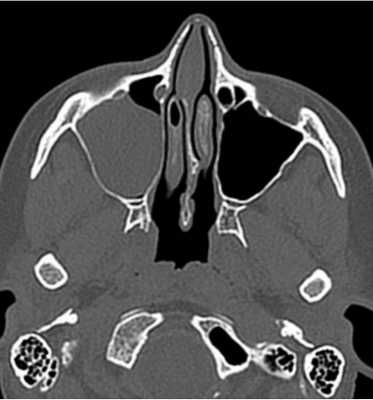

Снимки МСКТ показывают контуры, структуру, плотность всех частей пазух. По фото врач может произвести оценку:

расположения носовой перегородки;

путей дренирования синусов;

симметричности сторон носа и пазух;

степени пневматизации придаточных полостей;

состояния слезных протоков.

КТ дает изображения в поперечной (аксиальной) проекции. В специальной программе фото можно увеличить и рассмотреть мельчайшие детали. При помощи реформатирования рентгенолог реконструирует картинку в желаемой анатомической плоскости. Чаще всего это две дополнительные проекции - корональная (фронтальная) и сагиттальная (делит объект на левую и правую части). Также есть возможность создать объемную модель, отрезать «лишние» фрагменты, что упрощает изучение области интереса и облегчает трактовку данных.